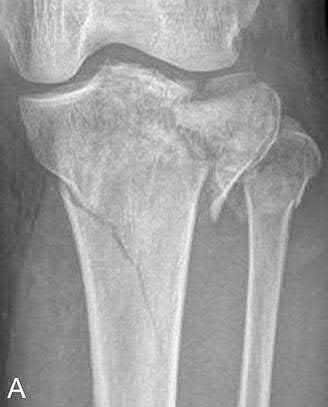

This patient presents with a Schatzker IV tibia plateau fracture with lower extremity neurologic deficits. The next best step would be to investigate for an acute vascular injury with ankle-brachial index measurements.

Fracture-dislocations of the knee must be suspected with all Schatzker type IV injuries as this fracture pattern is usually associated with high energy trauma. Identifying this injury should prompt a thorough assessment of the neurovascular structures across the knee. After closed reduction and emergent immobilization of the knee, ankle brachial indices (ABI) must be immediately performed. If

Knee dislocations are associated with popliteal artery injury in 18-45% of cases and range from intimal tears to complete transection. Amputation rates of 85% have been reported if revascularization is delayed greater than 6 to 8 hours.

Neurologic injury occurs in 15-40% of cases and is most common after posterolateral dislocation. The peroneal nerve is more commonly injured.

Rihn et al. reviewed the acutely dislocated knee. They recommend a vascular consult if pulses are weak, or ABI is compromised. They warn that in arterial injury, pulses, temperature and capillary refill can be normal. If the limb remains ischemic, surgical exploration and revascularization is indicated.

Medina et al. systematically reviewed neurovascular injury after knee dislocation in 862 patients. Vascular injury rate was 18%, and nerve injury rate was 25%. Repair was performed in 80% of vascular injuries, and amputation in 12%. The most vascular injury was seen in KDIIIL injuries (32%) and posterior dislocation (25%).

Figure A is an AP radiograph of a posterior knee dislocation. Figure B is a lateral showing the same injury.